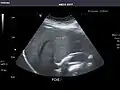

Spleen -

Spleen: Normal in size.